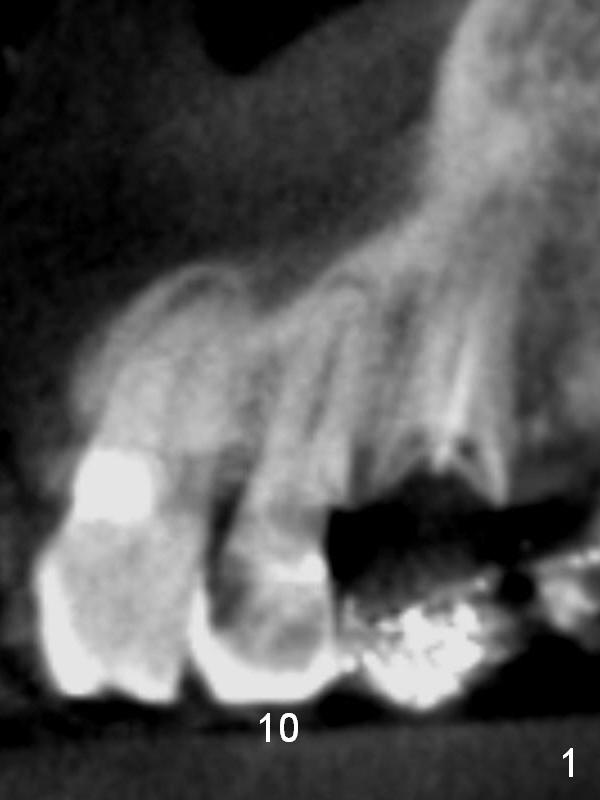

A 70-year-old man (CK) has history of several tooth fracture after RCT. When the tooth #10 develops pulpitis (Fig.1 CBCT sagittal section), he is reluctant to accept RCT. With several upper right and upper left implant placement, the affected tooth may not be so vulnerable to fracture. RCT will be tried first. If the caries proves to be too extensive (Fig.2 (coronal section) *), the tooth will be extracted with socket shield technique. Effort will be exerted for complete apex removal, followed by Metronidazole socket treatment. A 3.8x13 mm UF implant is placed; an angulated or gold coated abutment may be required (Fig.3). Bone density is 500-600 HU.